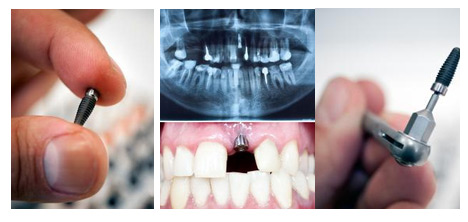

百元植体 种植牙颠覆底价

瑞典诺贝尔、瑞士ITI等欧美种植体品牌一直是种植界的翘楚,凭借出色的初期稳定性、生物相容性、高成功率成为缺牙患者更信赖的品牌,但价格昂贵,一颗植体就要上万元,很多条件一般的顾客负担不起。

正逢康贝佳口腔集团9周年庆典,感谢大连市民的一路同行,康贝佳携手百强厂商共同推出大幅让利活动。多种欧美高端种植体品牌第二颗仅100元,诺贝尔植体还可享终身质保。

【牙齿种植】:进口植体特价3800元/颗(限量200颗)